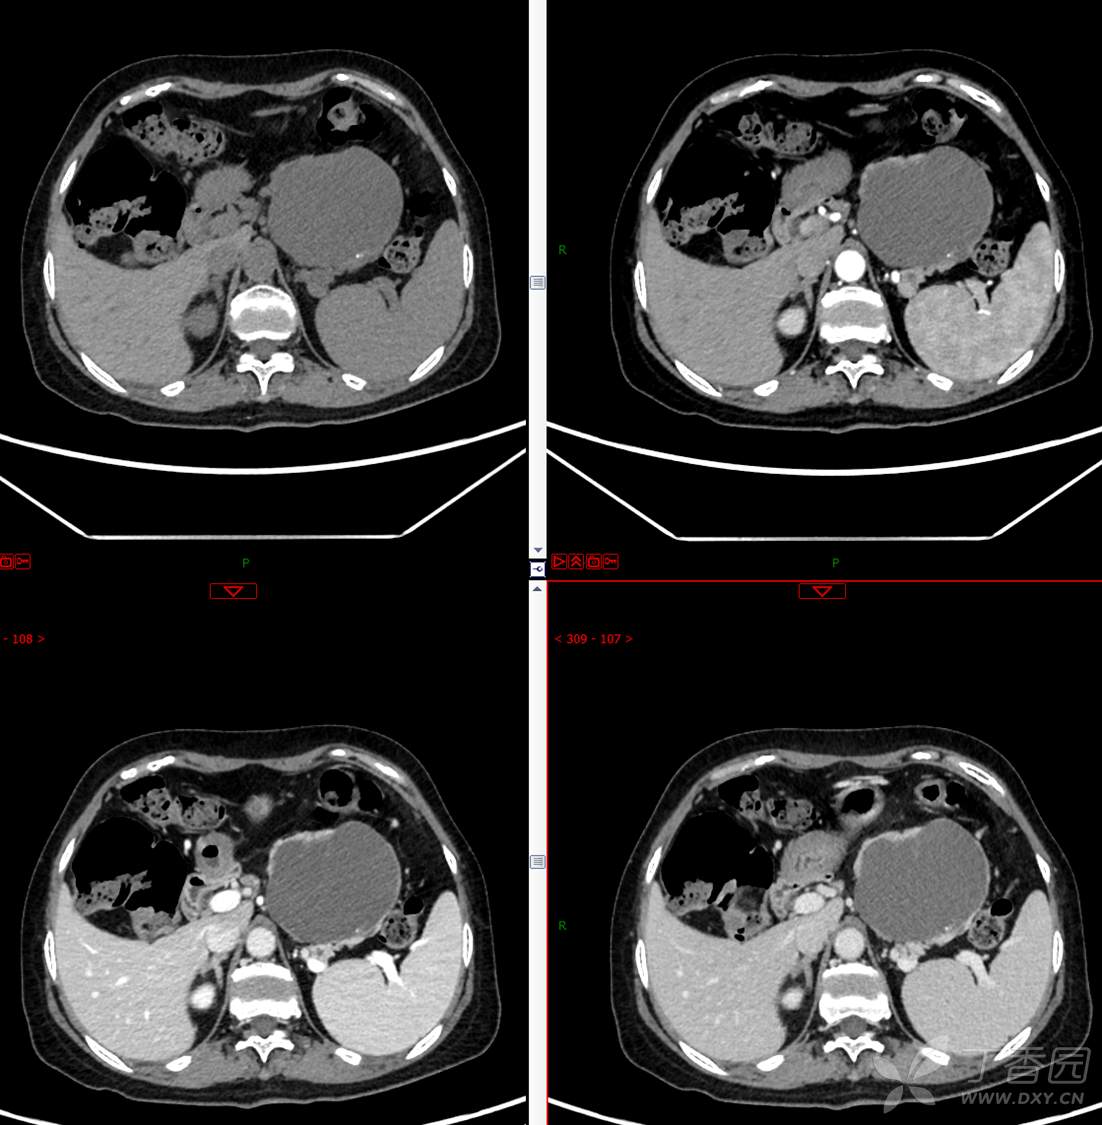

中老年女性胰腺占位,“奶奶瘤”or“妈妈瘤”?请分析领丁当!

主 诉:发现胰腺占位性病变3月

现病史:患者3月前就诊于**市人民医院行腹部增强CT发现胰尾占位性病变,无腹痛、腹胀,无恶心呕吐,无黄疸,无呕血黑便,无胸闷憋气,无寒战高热,未行特殊治疗